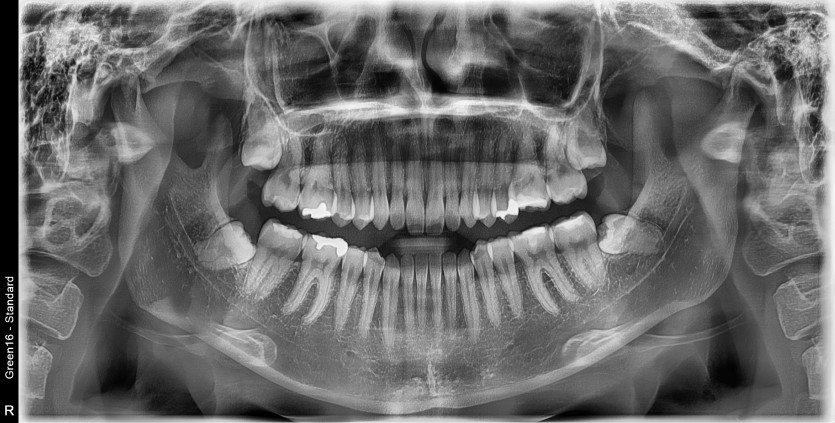

#28,38 사랑니 발치

구강 외과 전문의가 당일 발치하였습니다.